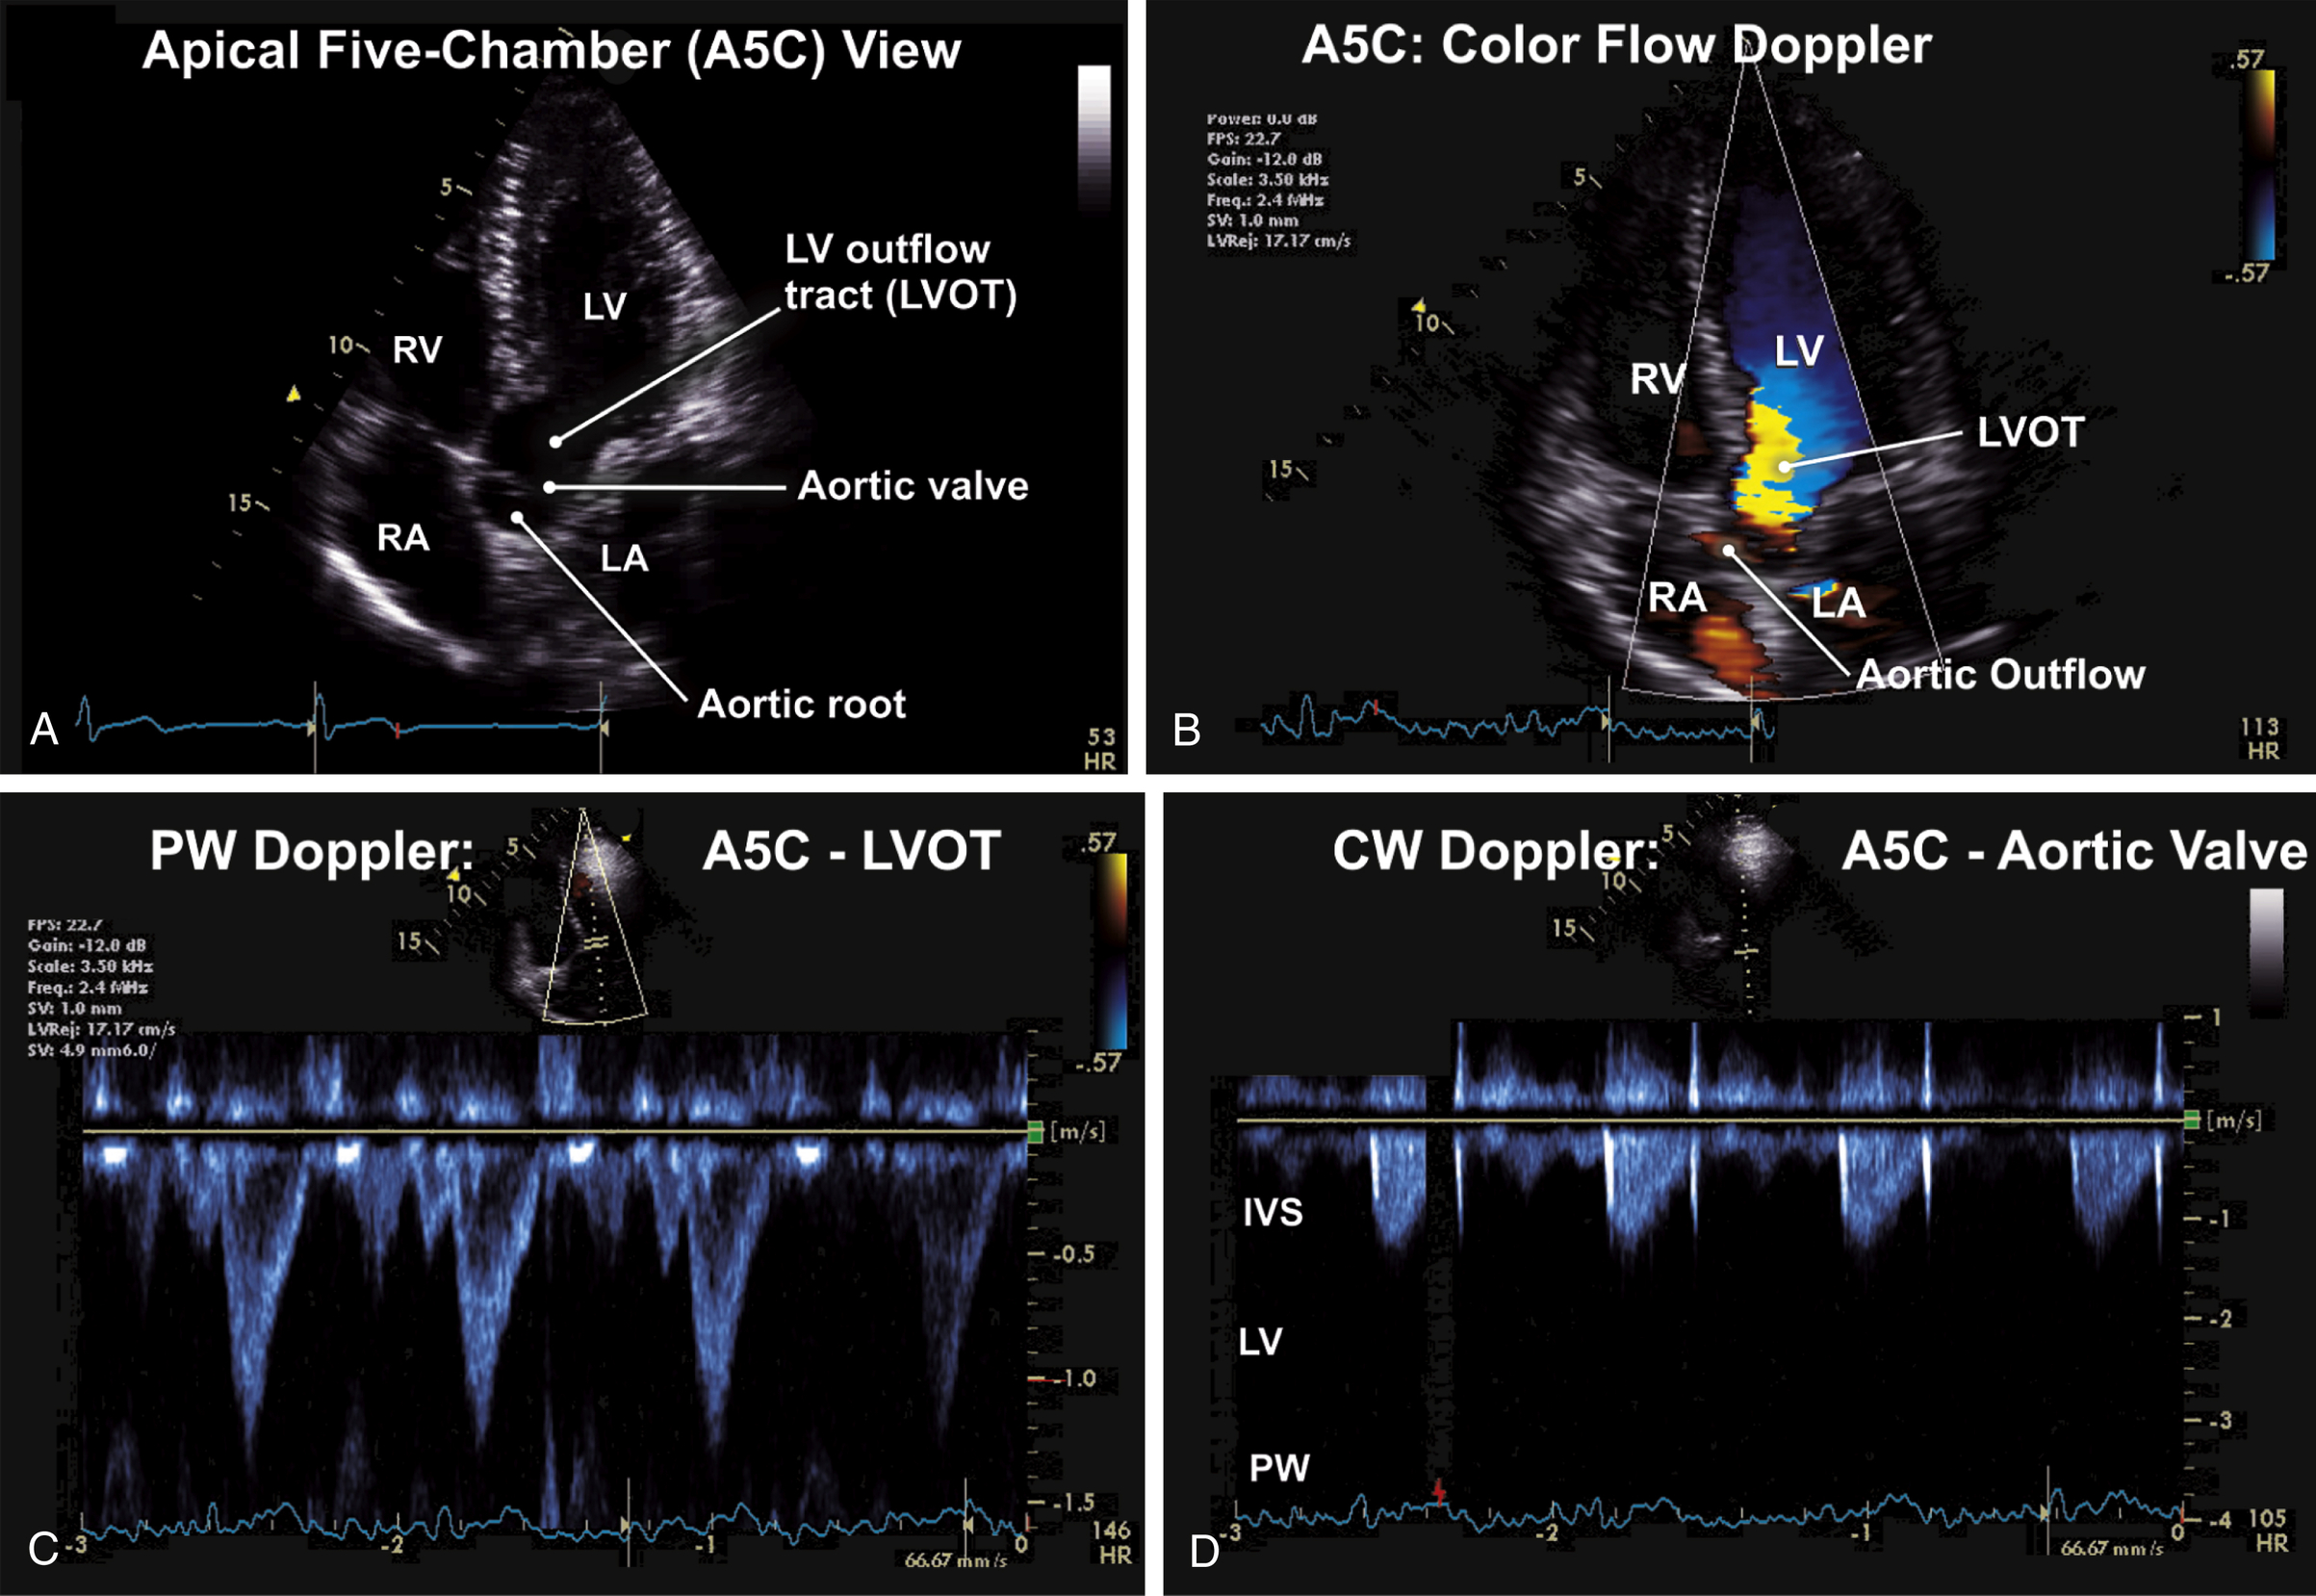

Apical Views (see Figs. 9.5–9.8)

| Transducer Position (Window) | 2d ± M-Mode ± 3d | CFD | Spectral Doppler Pw, Cw | Tissue Doppler Imaging (Tdi) |

| Apical five-chamber view (A5C) | 2D visualization of the AV-Zoom on the valve | CFD to the AV | PW Doppler of the LVOT (1–2 cm) from the valve leaflets, closing AV click CW for transaortic velocities | |